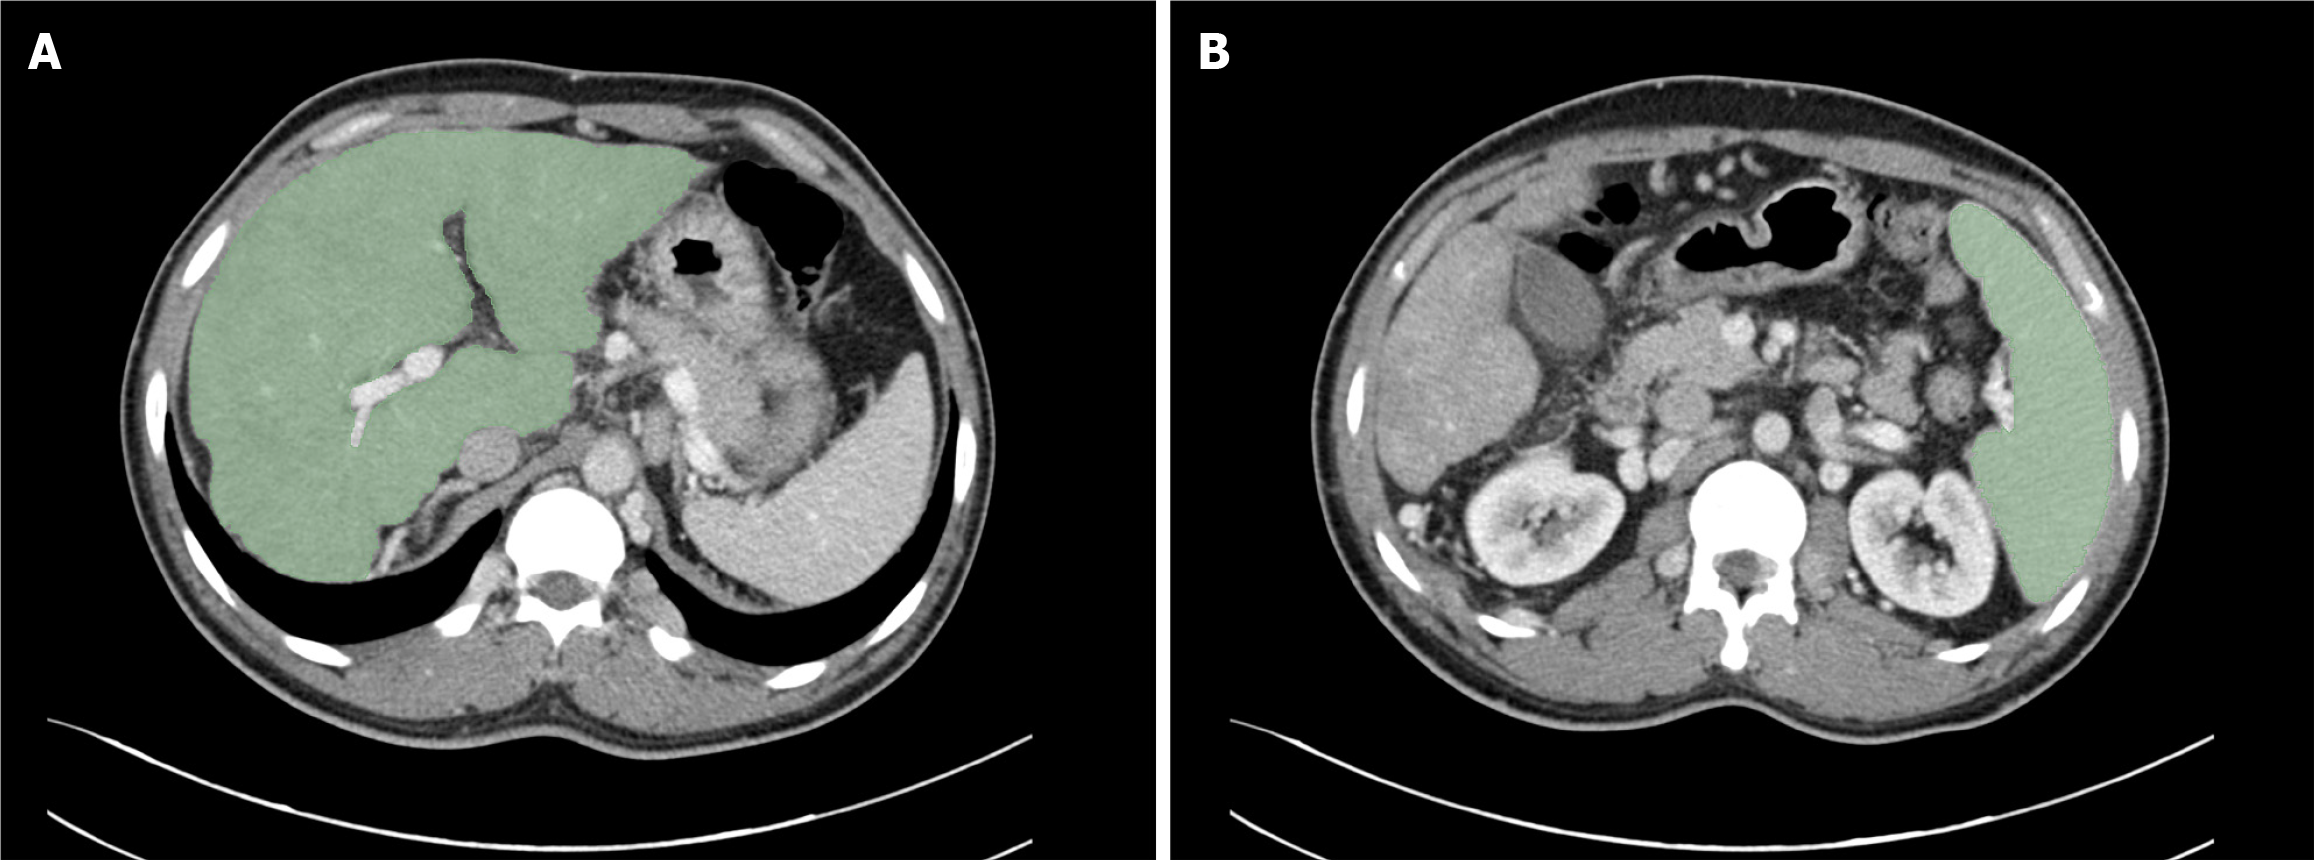

Two regions of interest (ROIs) were manually delineated at the hepatic (Figure 2A) and splenic (Figure 2B) hilum levels using 3D Slicer (version 5.6.1). Two experienced radiologists (each with > 7 years of experience) independently seg

In terms of diagnostic methods, this study used portal venous phase contrast-enhanced CT, which not only facilitates the diagnosis of BCS but also effectively evaluates GEVs, providing a comprehensive assessment of patients[30,31]. Compared with traditional endoscopy, enhanced CT offers noninvasive, highly sensitive and simultaneous evaluation of hepatic and splenic hemodynamics[32-34]. This imaging technology serves as a reliable alternative for patients unsuitable for endoscopy, reducing discomfort and potential complications during examinations and providing crucial patho